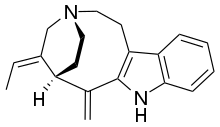

Indoles

- 18-Methoxycoronaridine

- 7-Acetoxymitragynine

- 7-Hydroxymitragynine

- ψ-Akuammigine

- Akuammidine

- Akuammine

- Coronaridine

- Eseroline

- Hodgkinsine

- Ibogaine

- Mitragynine

- Mitragynine pseudoindoxyl

- Noribogaine

- Pericine

- Pseudoakuammigine

Structures

| Indoles | ||||

|---|---|---|---|---|

|

7-Acetoxymitragynine |

|

Akuammidine |

|

|

|

-Mitragynine_Structural_Formula_V1.svg.png.webp)

|

|

|